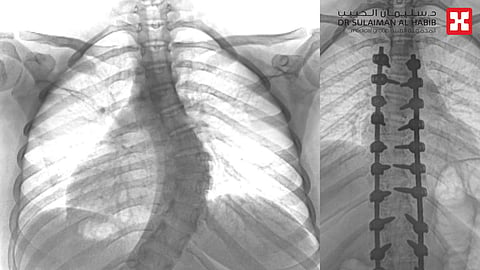

وأجرى لها الفريق الطبي، حزمة من التحاليل والفحوصات الطبية الدقيقة، التي أظهرت إصابتها بحالة انحراف "جنف صدري" بدرجة الـ"47" للفقرات الصدرية وقطني بدرجة "50"، ودرس الفريق الطبي الحالة على ضوء نتائج الفحوصات والتحاليل، وخلص إلى ضرورة التدخل الجراحي لعلاج العيوب، والحد من المضاعفات، وأخضعت الفتاة لعملية جراحية، تم فيها تقويم العمود الفقري وتثبيت ودمج الفقرات، باستخدام "22" من البراغي والقضبان المعدنية، والطعوم العظمية الصناعية، واستمرت العملية لـ"6" ساعات متصلة، وشارك فيها فريق تخدير متمرس وفريق تمريض ماهر، واستخدمت فيها مجموعة من أحدث الأجهزة الطبية، كجهاز مراقبة الأعصاب، وأمضت المراجعة ليلة واحدة تحت المراقبة بالعناية المركزة، ومن ثم نقلت إلى جناح التنويم بعد العملية، حيث بدأت في التحسن بشكل متسارع إذ استطاعت الوقوف والمشي خلال "24" ساعة، مع فريق العلاج الطبيعي المتمرس، كما أن طولها مع النجاح الكبير للتعديل زاد بضع سنتيمترات، وخرجت من المستشفى وهي بصحة جيدة.